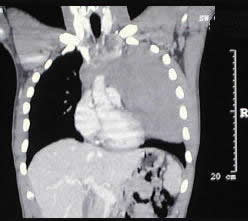

un paciente joven, con un gran tumor del mediastino anterosuperior de rápido

crecimiento, correlacionando su tamaño entre la radiografía

del tórax y los hallazgos tomográficos realizado 15 días

después, y las condiciones físicas al momento de su intervención,

con gran dificultad respiratoria.